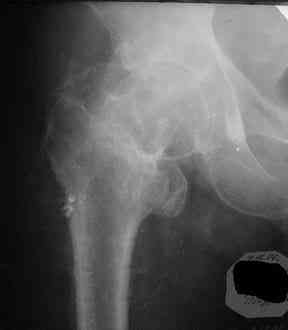

Все-таки хочу поделиться раз затронулась тема, может кому-нибудь и сгодиться. Это пример из области скорее трудноудаляемой. Пациент 50 лет, травма (низкоэнергетическая) 1,5 года назад. Оперирован через неделю (винт отечественный). Через 4 месяца выполнен контрольный снимок, сразу же возник вопрос: почему винт не телескопировался? Вопрос в общем-то так и остался без ответа.

При удалении (наркоз) после неимоверных усилий пришлось выкрутить фиксатор единым блоком и только тут все встало на свои места. См. фото.

Грустно+ Вот какие сюрпризы преподносят иногда коллеги.